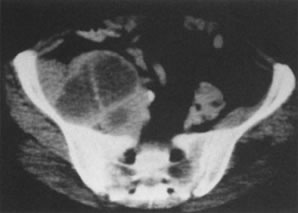

CT scans are inaccurate for determining parametrial invasion. However, if the nodes are larger than 1.5 cm, para-aortic node metastases can be detected in as many as 91% of women.39 CT scans should be done with intravenous contrast to give optimal information (Fig. 5). However, CT scanning is seldom beneficial in evaluating patients with small-volume disease.40 The specificity for detecting lymph node metastases is high, but the sensitivity is low.38,41 CT is correct in evaluating 92% of lesions staged IIIB through IVB.42–44 Evaluation of enlarged lymph nodes should be complemented by CT-guided fine-needle aspiration. The results of these tests cannot be incorporated into FIGO staging.

Fig. 5. Computed tomography with contrast in a 44-year-old woman. This necrotic node deviating the ureter medially at the pelvic brim was not palpable in this patient with a stage IB (1 cm) adenosquamous cell carcinoma of the cervix.